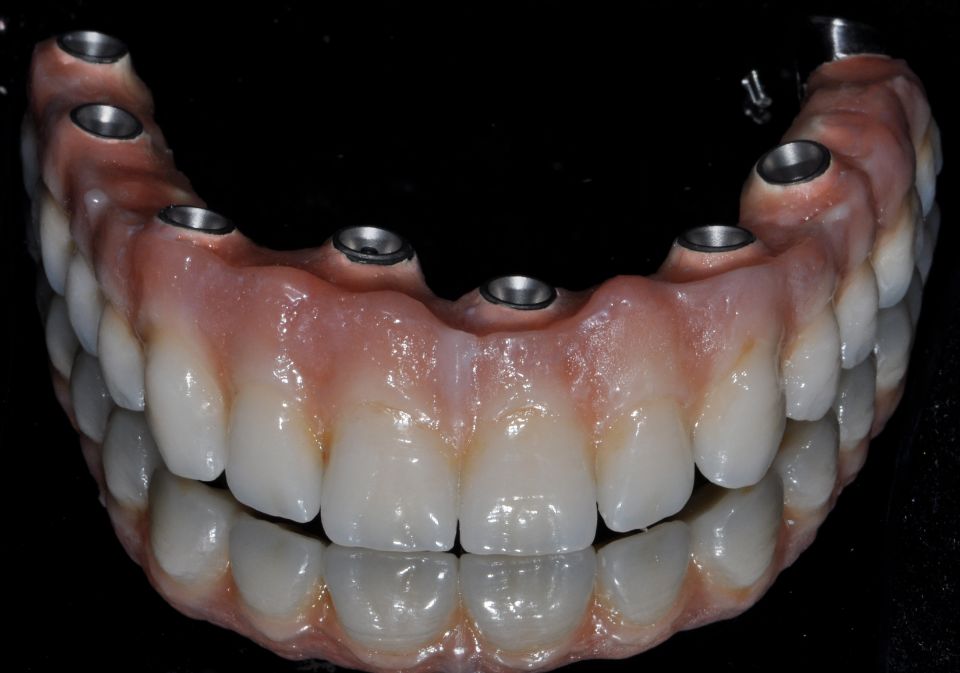

Rehabilitación protésica

La rehabilitación oral es la parte de la odontología que se preocupa de devolver la estética y armonía oral mediante prótesis dentales, siempre buscando una oclusión y función correcta. Combina de forma integral las áreas de prótesis fija, prótesis removible, operatoria, oclusión e implante dental.

Al realizar el plan de tratamiento, adecuado al paciente, se intentará recuperar su salud bucal a través de las técnicas más modernas de rehabilitación; estableciendo una estrecha relación con las demás disciplinas de la odontología, como periodoncia, endodoncia y ortodoncia. Para lograr el mejor resultado.

Mediante las técnicas actuales de odontología se consigue hacer dichas rehabilitaciones mediante prótesis fijas sobre dientes o implantes dentales en más del 95% de los pacientes, con lo que se evita la utilización de prótesis removibles que siempre son incómodas y en muchos casos imposibles de soportar.

Una de las técnicas más utilizada en la actualidad gracias a los avances tecnológicos, es la rehabilitación oral digital o flujo digital.

Rehabilitación con flujo digital

A través de las impresiones digitales en 3D realizamos rehabilitaciones protésicas mucho más perfectas y adaptadas desde el primer día, ya que la precisión del trabajo es mucho mayor, obteniendo resultados predecibles.

Se pueden realizar tanto en coronas sobre dientes naturales como sobre implantes, dando mayor comodidad y facilidad a los pacientes.